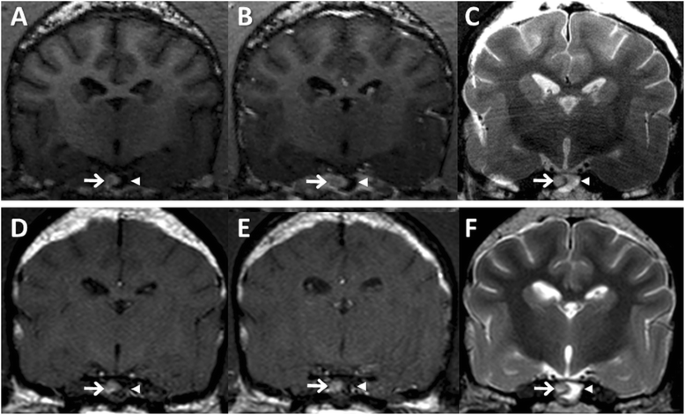

High-resolution MRI characteristics of a canine pituitary microtumor. Following initial 7 T MRI scan (a–c), a pituitary lesion was re-evaluated by 3 T MRI 6 months later (d–f). a Pre-contrast T1-WI showed the hypointense adenohypophyseal lesion (arrowhead), indicating a pituitary microtumor, and the hyperintense neurohypophysis (arrow). b Uniform contrast enhancement was observed on the neurohypophysis (arrow), while the adenohypophyseal lesion had no enhancement (arrowhead) on post-contrast T1-WI. c T2-WI revealed hyperintensity in the adenohypophyseal lesion (arrowhead) and isointensity in the neurohypophysis (arrow). At 6 month follow-up, MRI findings of the adenohypophyseal lesion (arrowhead) and the neurohypophysis (arrow) were not changed on pre- (d) and post- (e) contrast T1-WI and T2-WI (f), except for a slight increase in the size of the pituitary gland

The dog was treated with trilostane (3 mg/kg orally [PO], twice daily [BID]; Vetoryl; Dechra, Shrewsbury, UK), and then post-ACTH cortisol concentration had been maintained between 2 and 5 μg/dL. Six months after initial MRI, a pituitary lesion was monitored by 3 T MRI scan (Achieva 3.0 T multi TX; Philips Healthcare, Best, NL) with following sequences: pre- and post-contrast T1-weighted spin echo imaging (TR: 500 ms, TE: 12 ms, flip angle: 90°, matrix: 256 × 256, FOV: 150 mm, slice thickness: 3 mm, interslice gap: 0 mm) and T2-weighted turbo spin echo imaging (TR: 4000 ms, TE: 80 ms, flip angle: 90°, matrix: 304 × 294, FOV: 130 mm, slice thickness: 3 mm, interslice gap: 0 mm). Although the height (4.67 mm) and P/B ratio (0.31) of the pituitary gland were slightly increased, other MRI findings were not different from the first MRI scan (Fig. 2d–f). Presently, the dog is managed well without dermatological or neurological abnormalities.